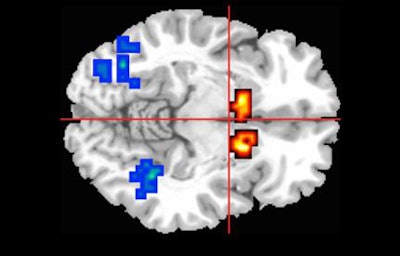

MRI shows activity (red and yellow areas) in the caudate region of the brain, which is affected in people with psychosis. Image courtesy of King's College London.All participants underwent MRI scans while performing a memory task to engage three regions of the brain involved in psychosis.

Among those at risk for psychosis, the subjects who were given cannabidiol showed less-severe abnormal brain activity than those who received a placebo, suggesting that cannabidiol can help readjust brain activity to normal levels.